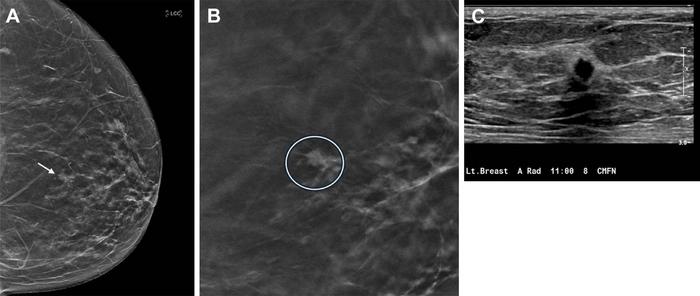

Most true-positive cancer cases detected by DBT presented as masses, while fewer presented as calcifications and asymmetries.